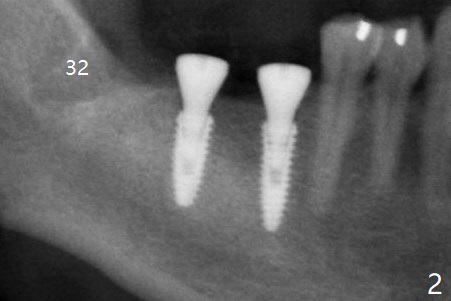

After infiltration and pdl anesthesia, the tooth #32 is extracted with elevators and forceps.  Drilling protocol per CBCT plan, no deviation (see instruction sheets). Implants are placed subcrestal: 4.0x11.5 mm at #30 and 4.5x10 mm #31 with >50 Ncm. Healing abutments (6x4 mm) are placed (Fig.1,2).  Resorbable suture is used to close #32 socket. Sensation returns. There is no hemorrhage.  Although the wound looks healing 4 days postop and the healing abutments have normal position (Fig.3), the patient complains of fair amount of pain.